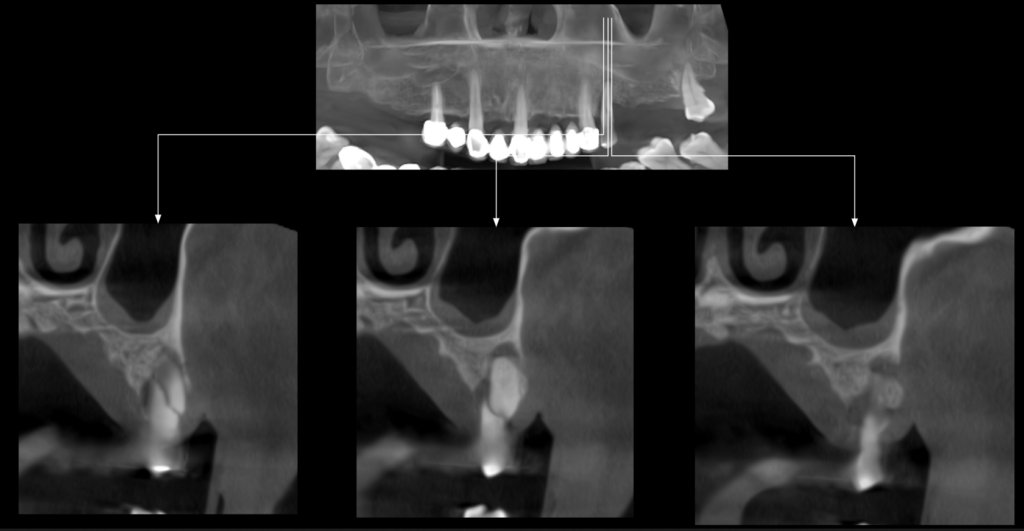

En la tomografía computarizada de haz cónico (CBCT) de ambos maxilares, evaluada mediante cortes axiales (Figura 2), transaxiales (Figura 3) y tangenciales (Figura 4), se observó una línea hipodensa de trayecto sinuoso que se extendía desde la superficie cervicovestibular hacia el tercio apical radicular palatino, comprometiendo el conducto radicular. Asimismo, se evidenció un proceso osteolítico perirradicular y pararradicular en el tercio medio radicular palatino, que ocasionaba adelgazamiento de la cortical de la tabla ósea.

CORTES TRANSAXIALES